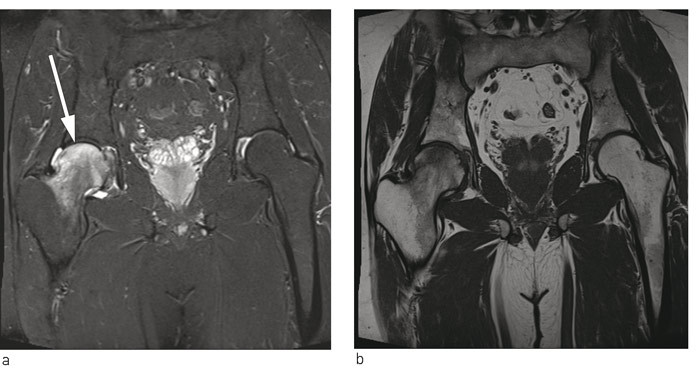

På bakgrunn av flere kasuistikker hvor man beskrev mulig effekt av peroral bisfosfonatbehandling ved benmargsødemsyndrom, startet vi med alendronat 70 mg en gang i uken (9). Pasienten ble fulgt opp med regelmessige telefonkonsultasjoner, og både smerter og funksjonsnivå bedret seg gradvis. Ved kontroll seks måneder etter symptomdebut var han smertefri og kunne belaste benet fullt. Ny MR-undersøkelse viste full tilbakegang av benmargsødemet i caput femoris, men noe ødem i acetabulum. Etter ytterligere tre måneder var MR bekken og hofteledd helt normalisert (fig 2). Bentetthetsmåling viste da T-skår –2,6, og –2,1 i henholdsvis høyre og venstre hofte. Videre oppfølging av endokrinolog viste vedvarende lett forhøyet PTH-nivå uten at det ble funnet noen sikker årsak til dette.

På MR-bilder er benmargsødem karakterisert av diffust utbredte forandringer i form av væskelignende signal fra benmarg med nedsatt signalintensitet på T1-vektede bilder og økt signalintensitet på væskesensitive sekvenser, f.eks. T2-vektede bilder med fettsuppresjon eller «short tau inversion recovery»-sekvens (STIR) (1).